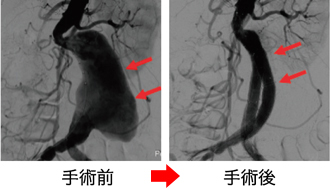

下肢閉塞性動脈硬化症に対するハイブリッド手術

血管内治療(赤): 狭窄した動脈にステントを挿入し、動脈を内側から押し広げる

外科手術(青): 閉塞した血管の血流を維持するため、人工血管を移植するバイパス術を行う